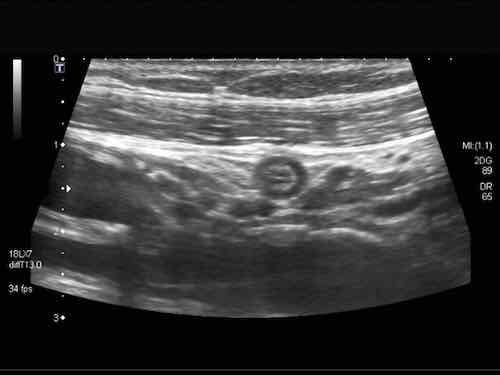

Đây là hình ảnh siêu âm của một trẻ 2 tuổi bị lồng ruột hồi manh tràng từng đợt, được khám trong khoảng thời gian giữa các cơn.

Hồi tràng với nhiều mảng Peyer sa vào manh tràng.

Hình ảnh siêu âm kinh điển của lồng ruột hồi-manh tràng ở hai trẻ khác nhau.

Trong cả hai trường hợp, đoạn hồi tràng bị lồng được định vị không đối xứng bên trong ống lồng ngoài, do mạc treo ruột tăng âm có chứa mỡ, bám vào hồi tràng và đi theo hồi tràng khi bị kéo vào trong.

Trong mạc treo, siêu âm cho thấy một hạch bạch huyết mạc treo (hbh) phóng đại ở cả hai.

Các hạch này phì đại như một phần của tình trạng tăng sản hạch bạch huyết toàn thân và khônghu trú trong lòng hồi tràng.

Do đó đây không phải là điểm dẫn đầu nguyên phát. Ở bệnh nhân bên phải, ruột thừa (mũi tên) cũng bị kéo vào trong.

Lưu ý cấu trúc đa lớp của thành bụng phía trước của phức hợp lồng ruột, đại diện cho ba lớp thành ruột bị gấp lại.